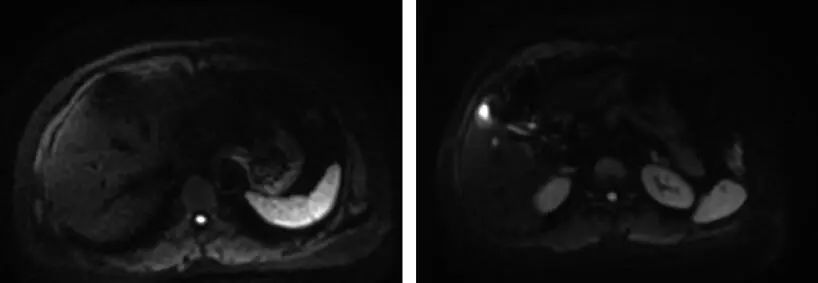

(2) 治疗予紫杉醇+顺铂+贝伐单抗治疗4 个周期后,肺部CT(图4):未见转移病灶。复查肝脏及盆腔MRI(图5):肝脏S2、S6 病灶消失,S4 病灶较前明显缩小。

图5 4个周期化疗+靶向治疗后上腹部MRI检查结果